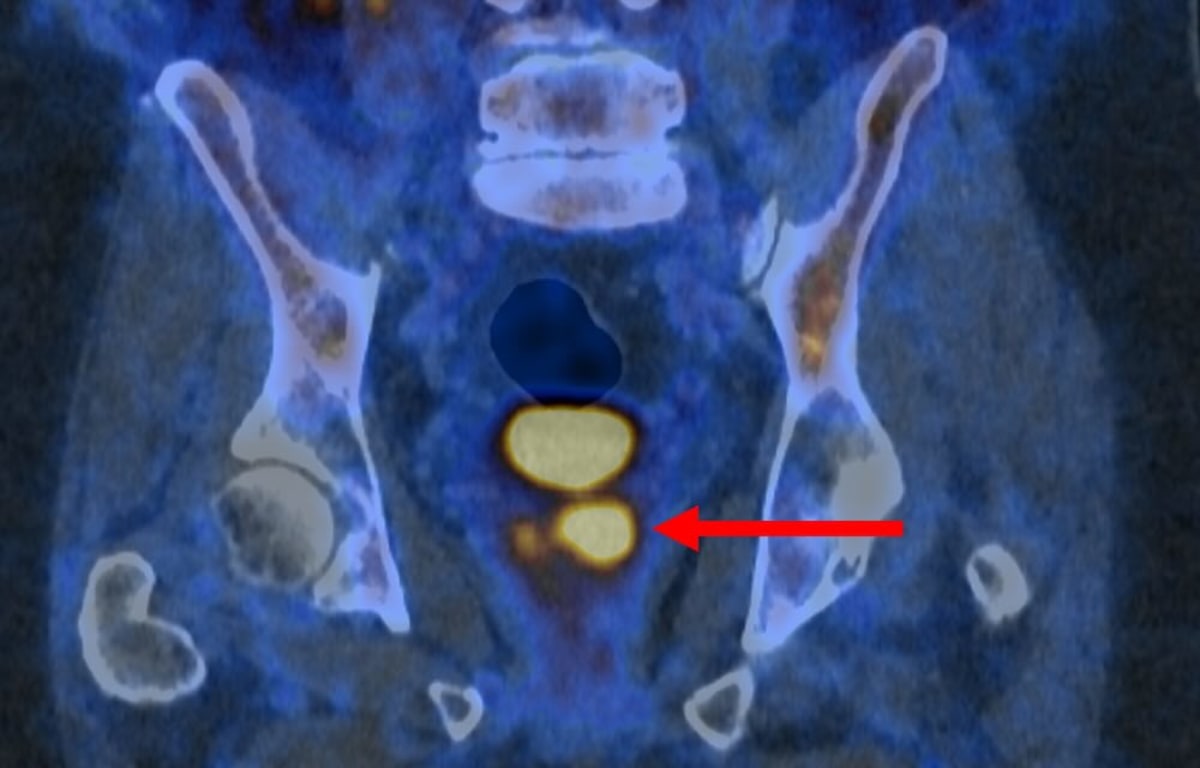

The PSMA PET/CT scan uses a special molecule that binds to prostate cancer cells, causing them to appear as bright spots on the imaging screen. Already available in Australia and parts of Europe, this test is changing how doctors diagnose one of the most common cancers in men.

"PSMA PET/CT scanning makes prostate cancer cells light up in a remarkable way, particularly in more aggressive cancers," Dr. Buteau explained. "It's rare to see such strong imaging that could be so powerful in the clinic."